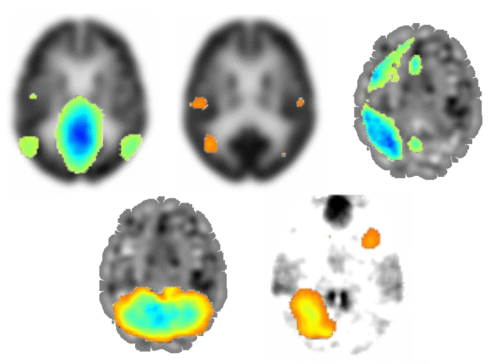

Član naše skupine, Mauro Namias, je skupaj z več soavtorji, med katerimi so tudi raziskovalci...